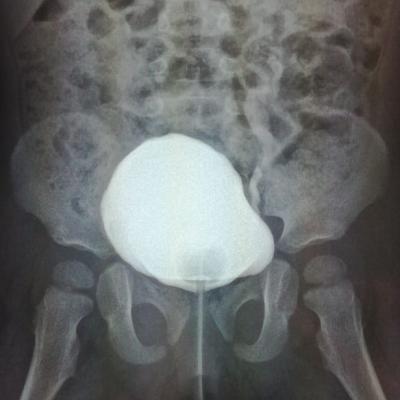

ПМР4степени,гипоплазия лев.почки

Здравствуйте.Ребенку 14.09.17г.р.сделали эндоскопическую коррекцию ПМР 4ст.второй раз ,хотя квота выписывалсь на сложную операцию.После коррекции ребенок стал мочиться еще реже и ухудшился ОАМ на четвертые сутки.

Здравствуйте!После таких вмешательств бывают преходящие нарушения мочеиспускания, и анализ мочи после инструментального вмешательства может ухудшиться(вопрос- как именно). Но, безусловно, Вам надо обратиться оперирующему урологу. Удачи!